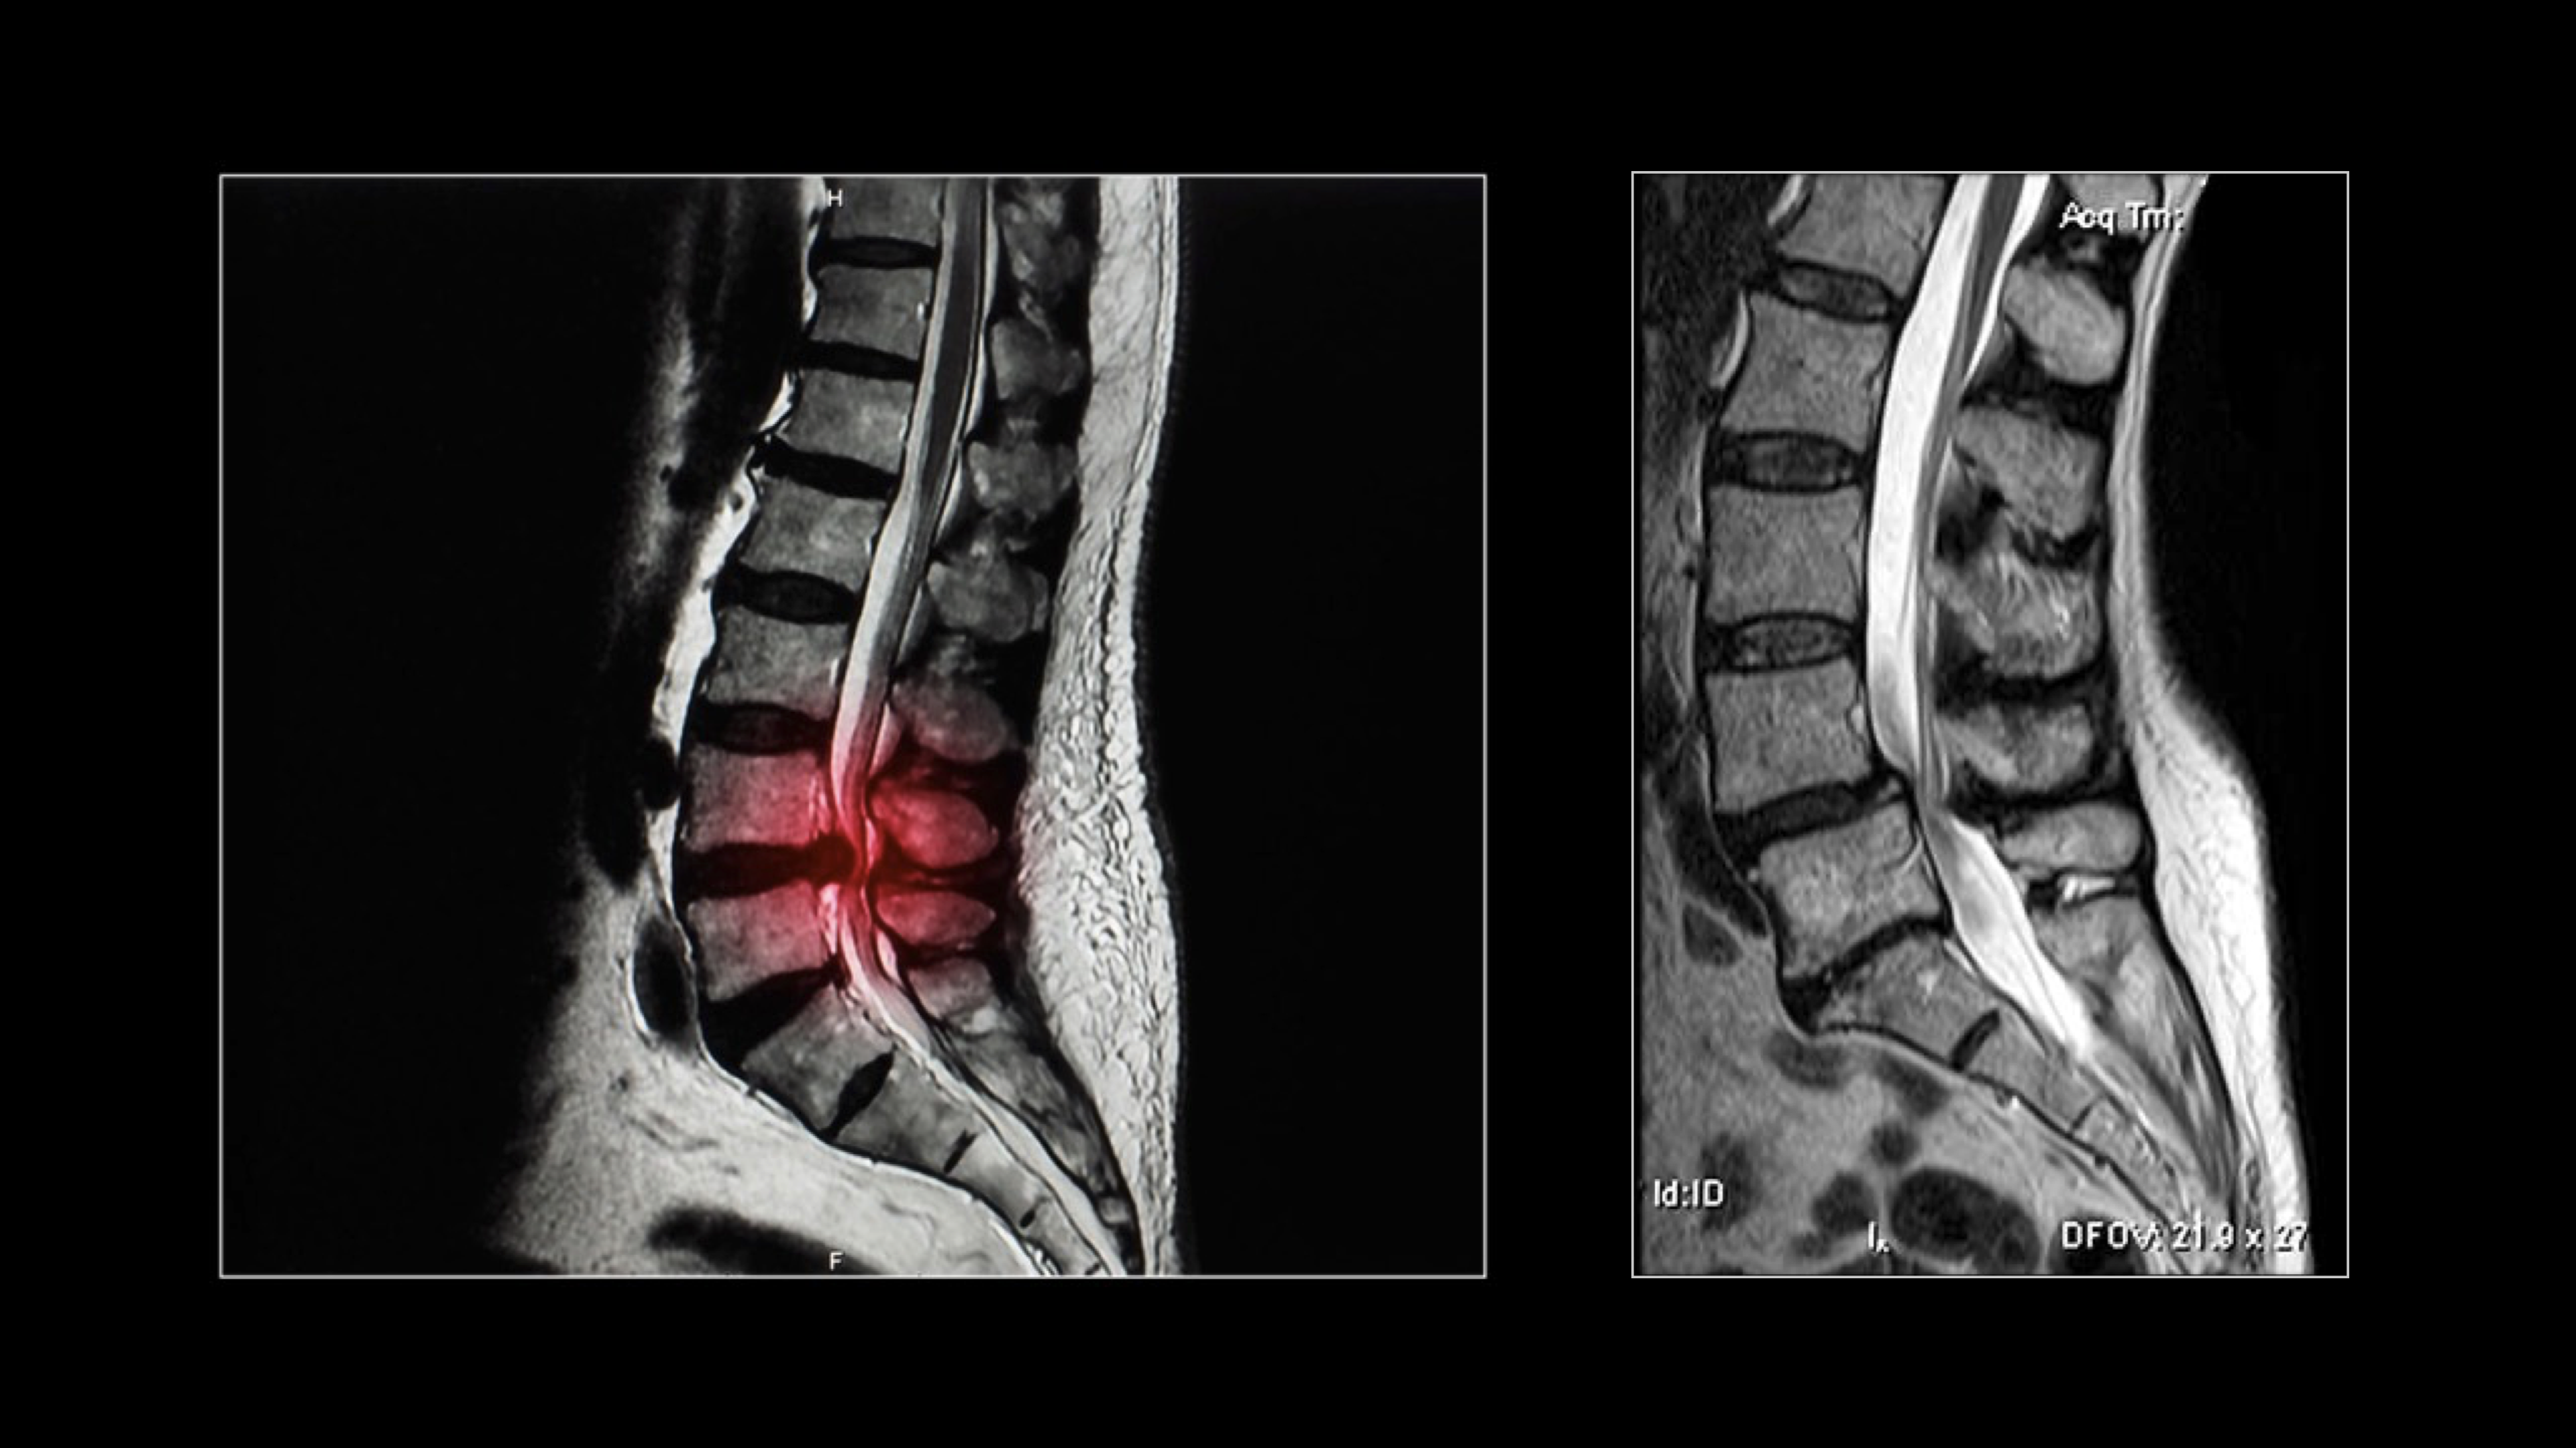

Hernia discal lumbar

Estenosis de canal lumbar